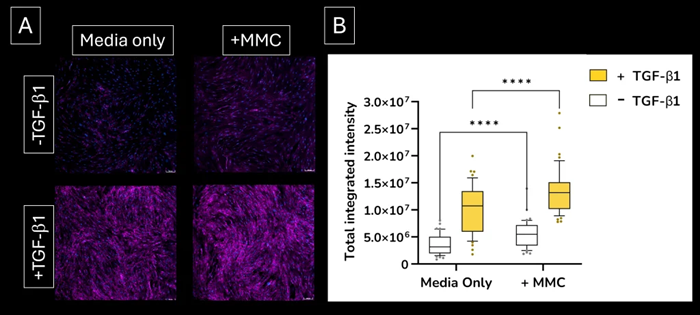

- The addition of a macromolecular crowder (MMC) agent to the culture medium creates a more in vivo-like environment and encourages the deposition of secreted extracellular collagen I, increasing signal sensitivity

Increased sensitivity. Addition of the macromolecular crowding (MMC) agent to the lung fibroblast culture medium increases the deposition of extracellular collagen I protein. (A) extracellular collagen I deposition. Images were acquired using the ImageXpress Confocal HT.ai imaging system (B) quantified expression levels of extracellular collagen I deposition. Image Credit: Newcells Biotech